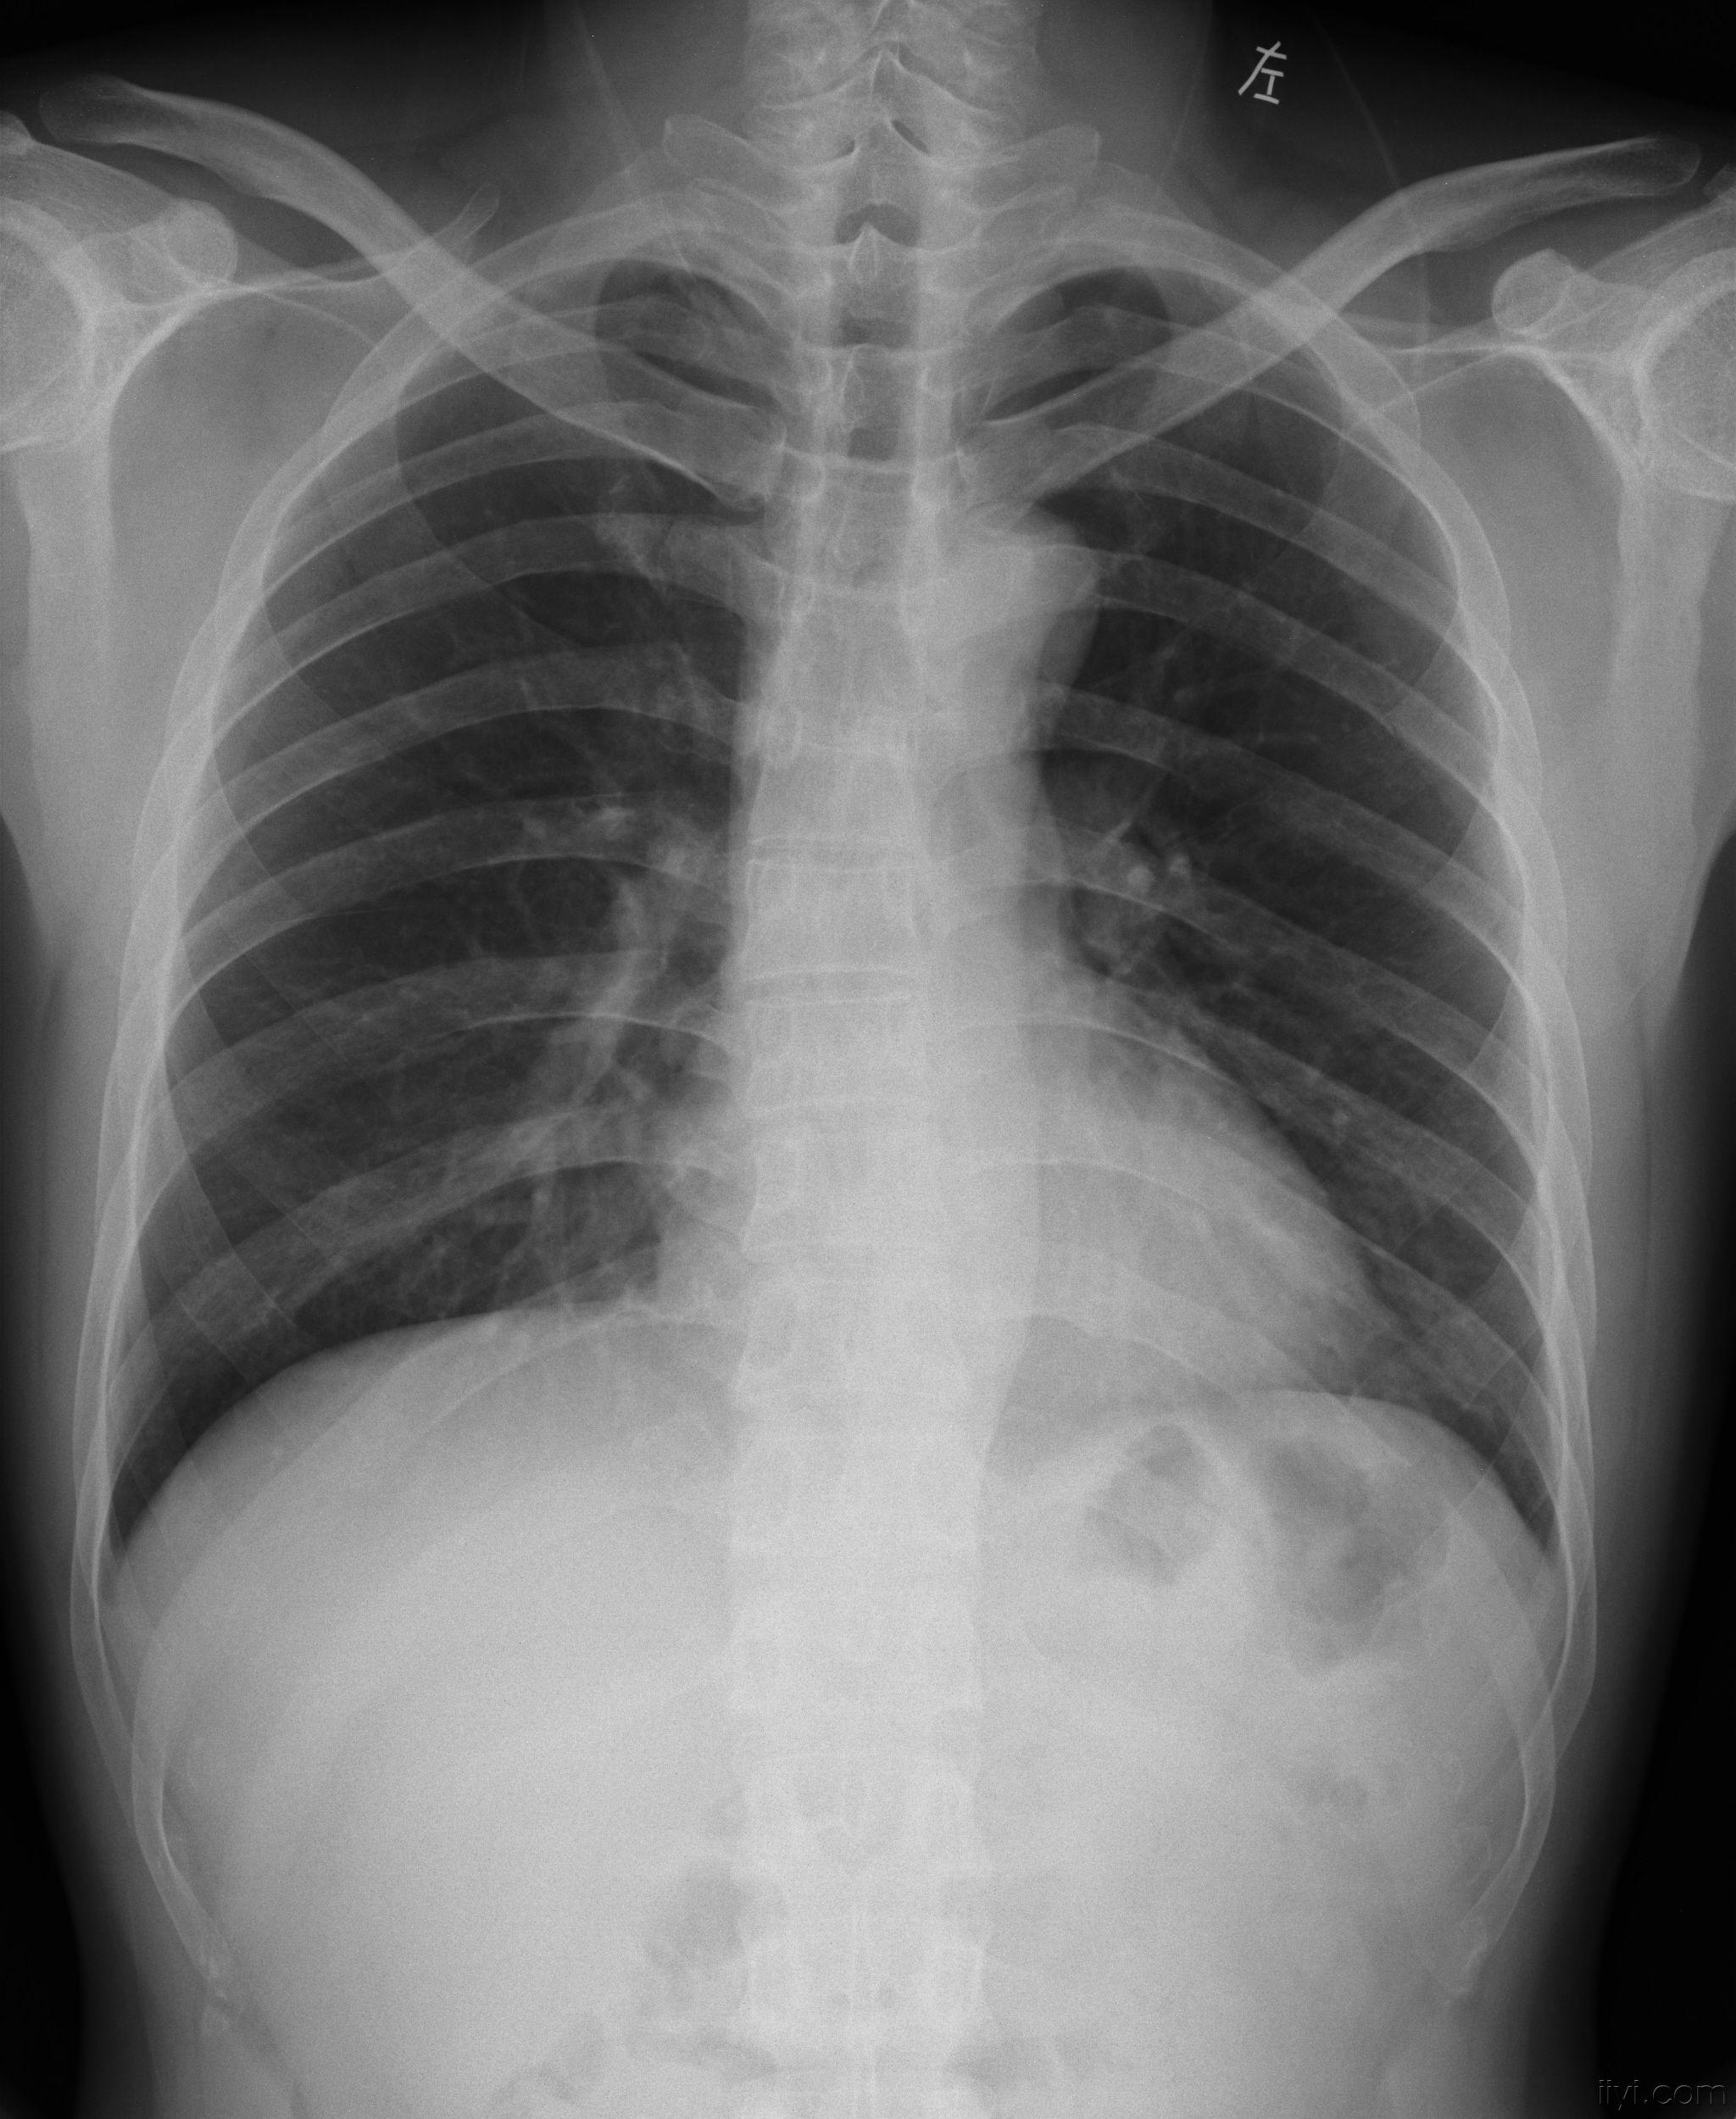

肋骨骨折的片子 医学影像学讨论版 爱爱医医学论坛

肋骨一根骨折的照片 第1页 一起扣扣网

断裂一根肋骨的ct图片 第1页 一起扣扣网

肋叉骨断了ct照片 第1页 要无忧健康图库

肋骨线性骨折ct图 第1页 一起扣扣网

断裂一根肋骨的ct图片 第1页 一起扣扣网